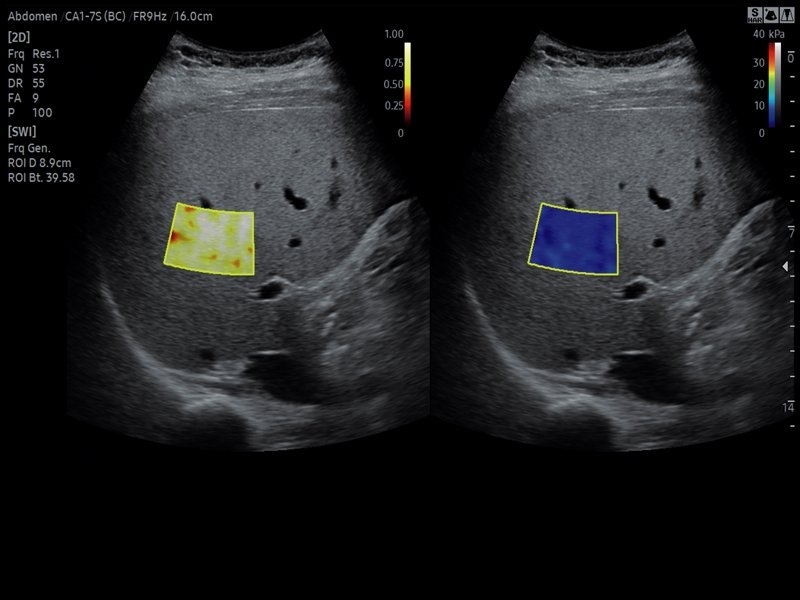

[RU] Ultrasound image №811: Liver in S-Shearwave Imaging™ mode (shear wave elastography).

Echogramm was received by ultrasound scanner RS85 (available for sale).